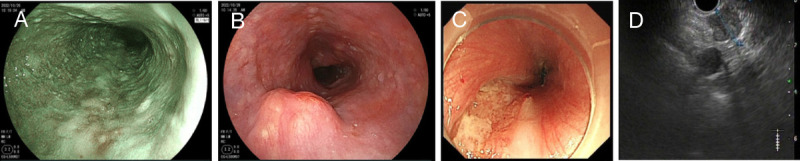

Occult synchronous multiple primary esophageal squamous cell carcinoma with mediastinal metastasis (with video).